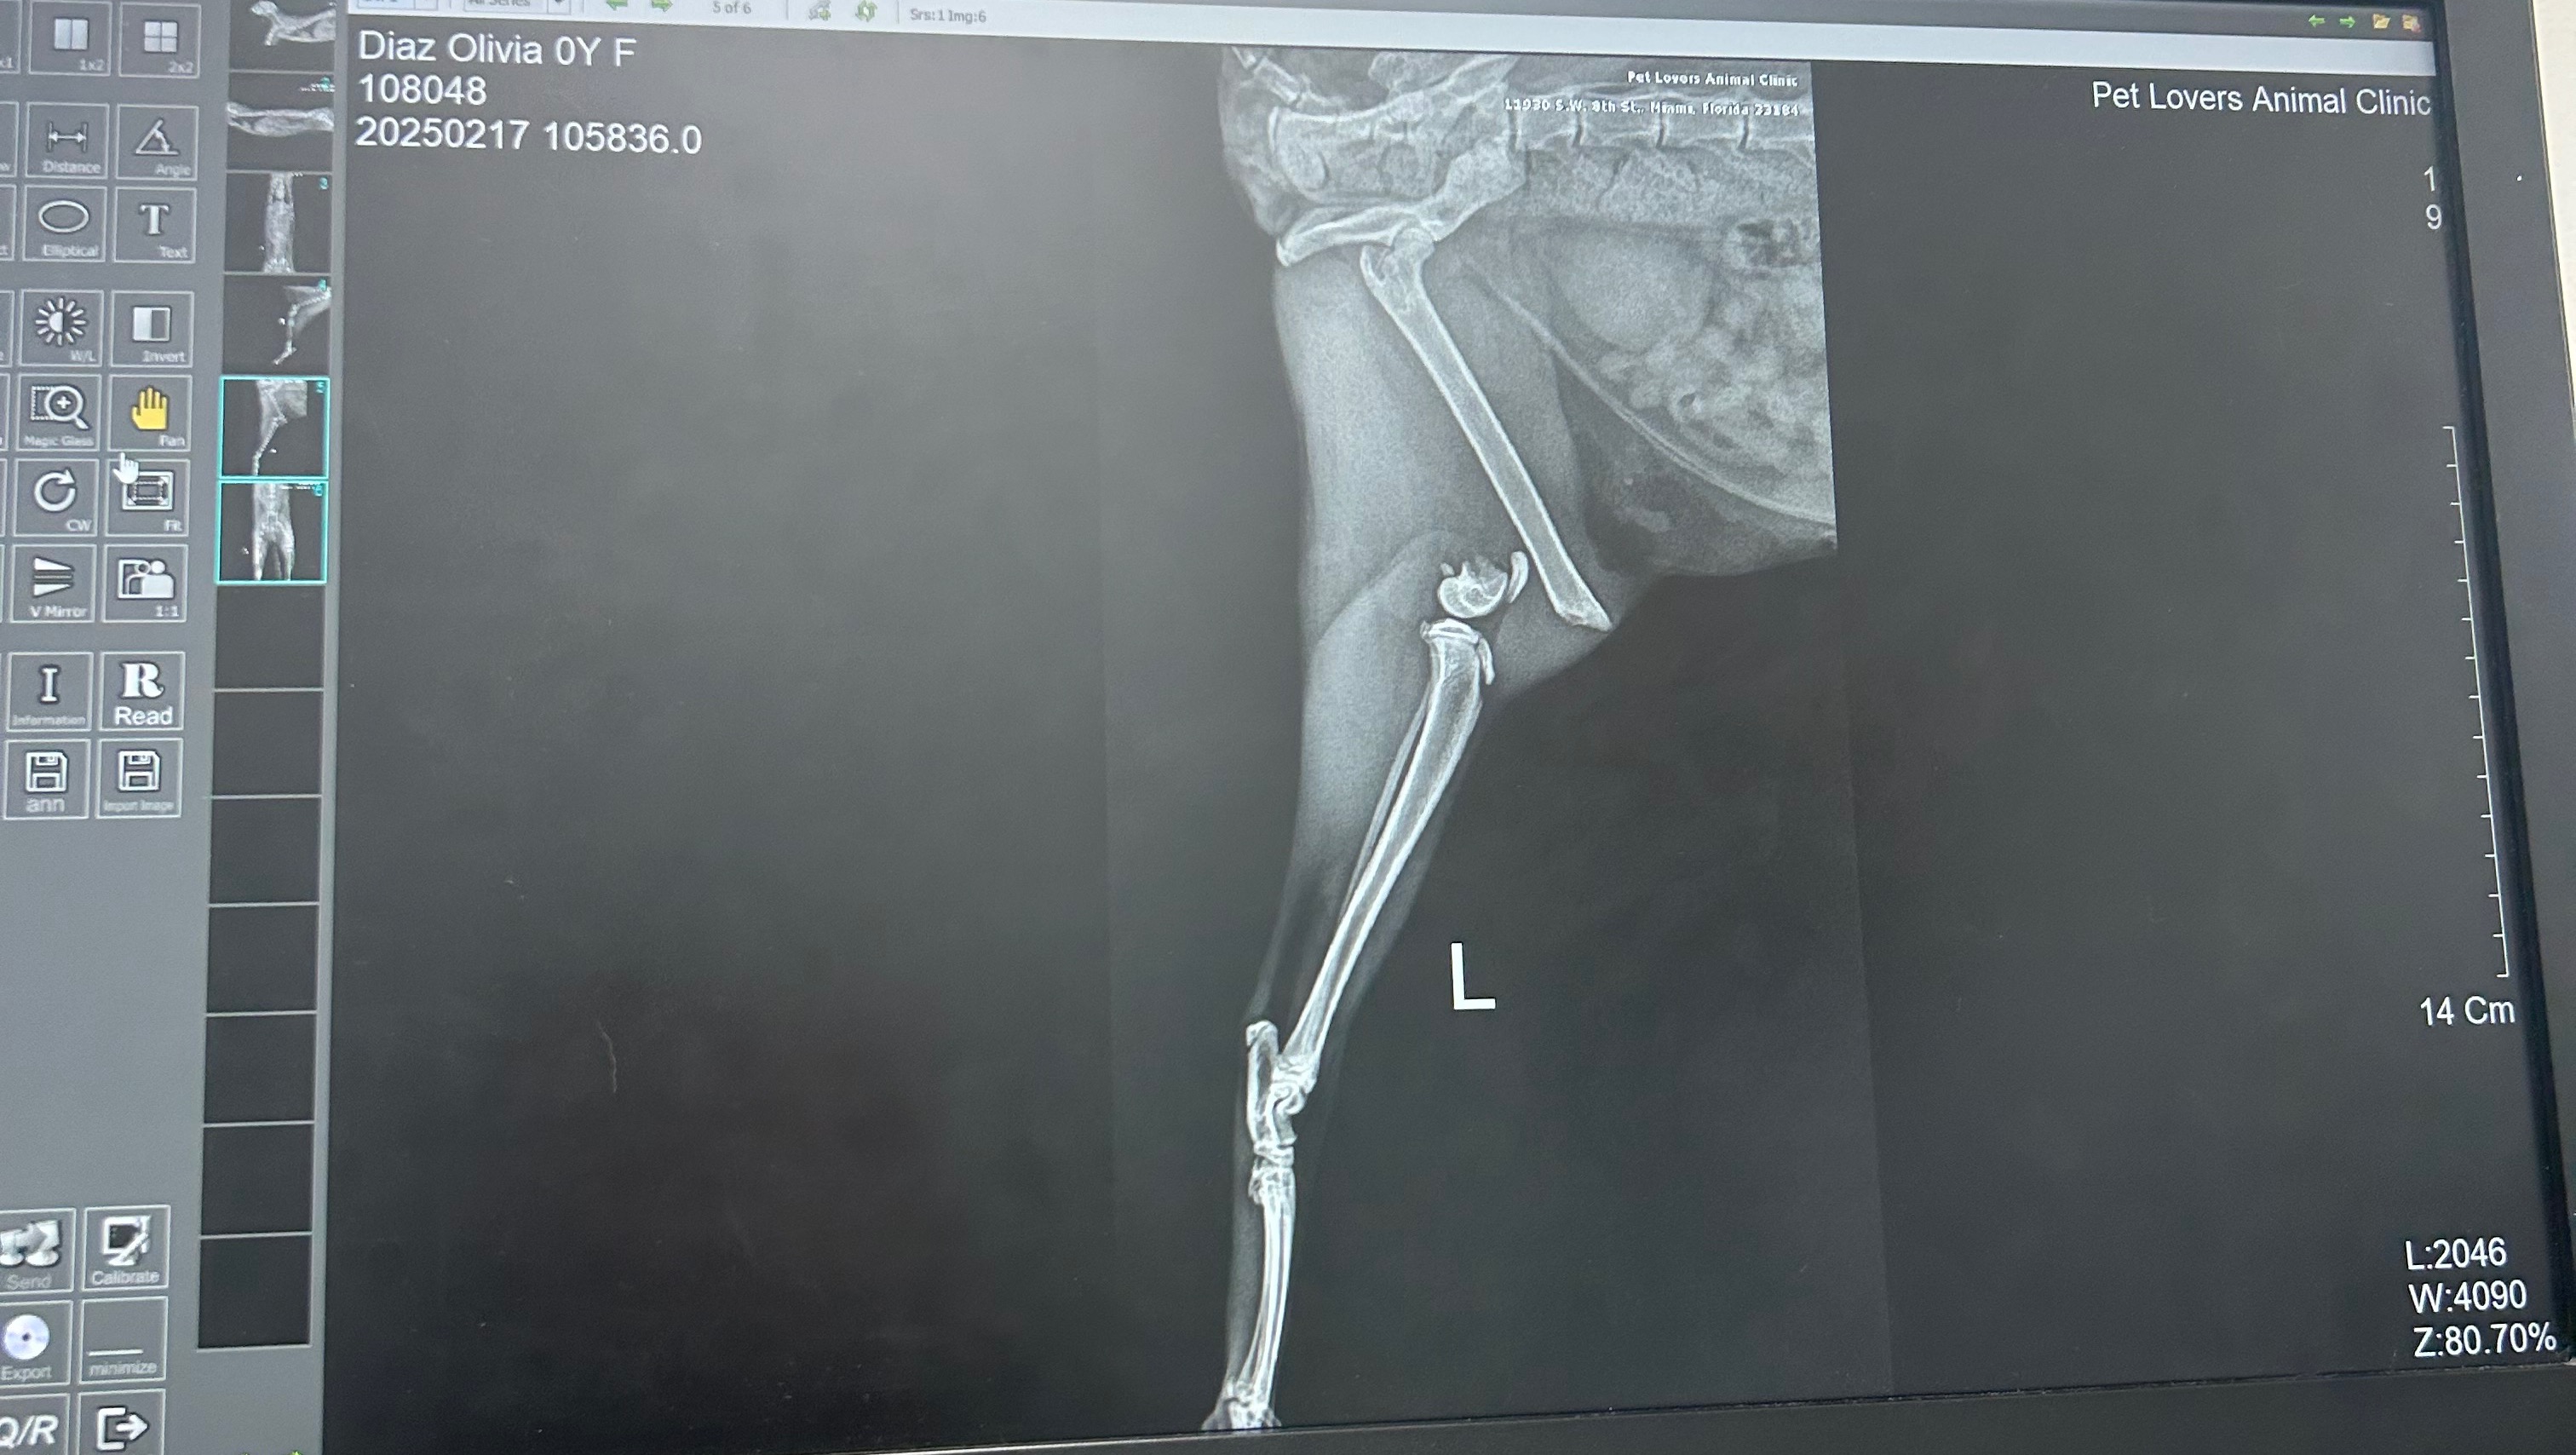

Hi, I’m Danna, Olivia’s owner, today Livie felt from the 5th floor of the apartment and she broke her leg, i took her to the Vet and they told me her surgery is going to be $2,059 Dollars + recovery and unfortunately i do not have the money right now, if she doesn’t get the surgery right away they’ll have to amputate her paw which is going to make her life miserable and really hard for her, if you can help me, i would truly appreciate it. -xoxo, Danna.